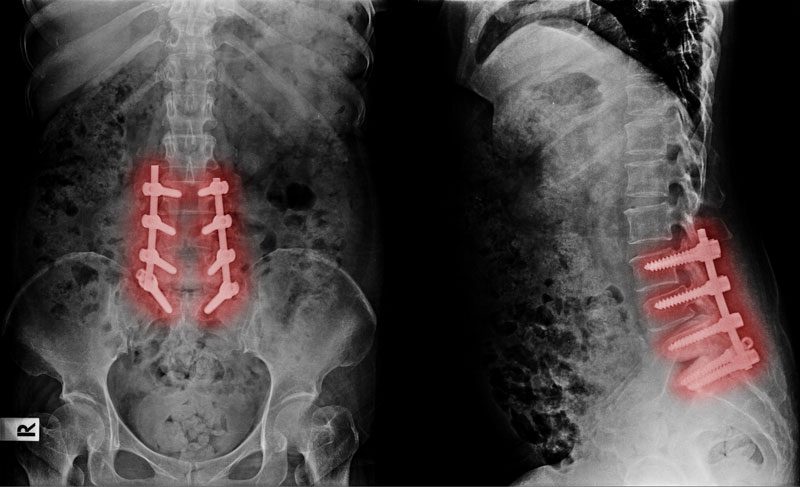

- КТ (анализ костных структур, положения имплантов).

- Рентген с функциональными пробами (при подозрении на нестабильность).